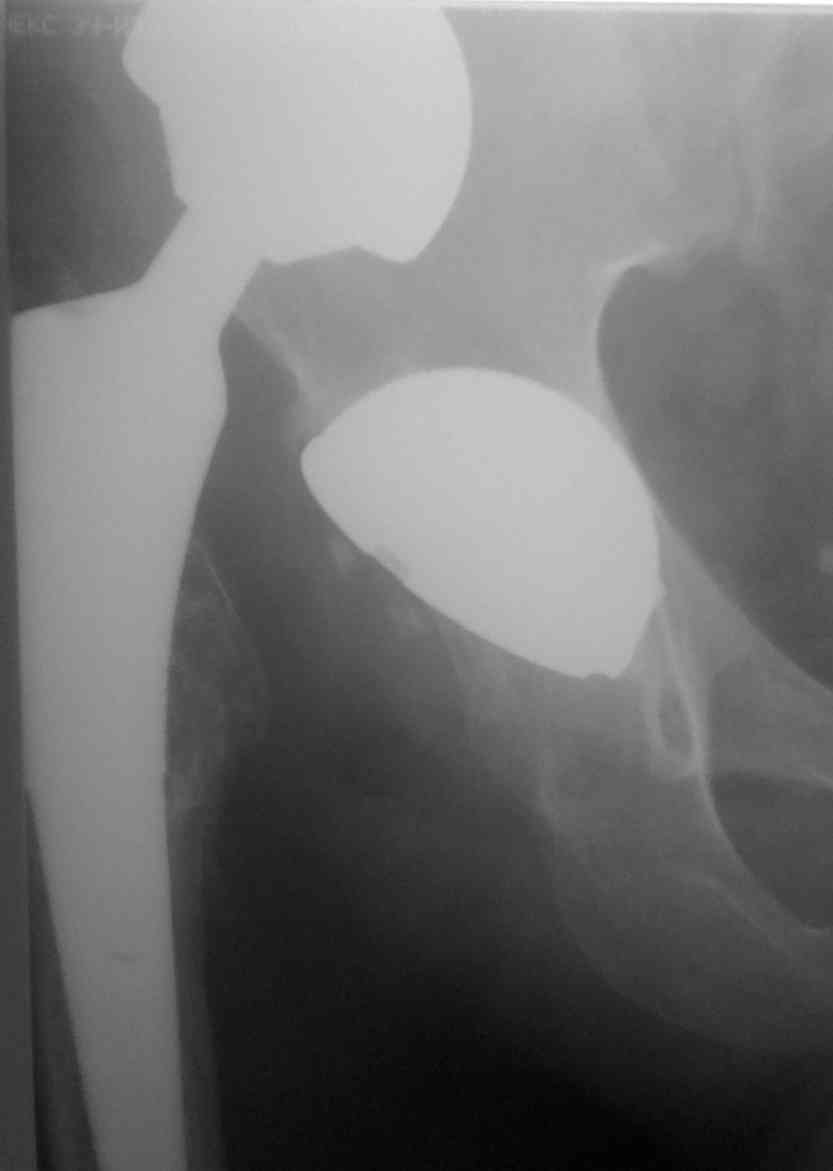

Застарелый вывих эндопротеза |

Пациент 40 лет, оперирован в апреле 2009. вывих в мае 2009г. За медпомощью не обращался. попыток устранения вывиха не было. ходит на костылях без опоры на конечность.